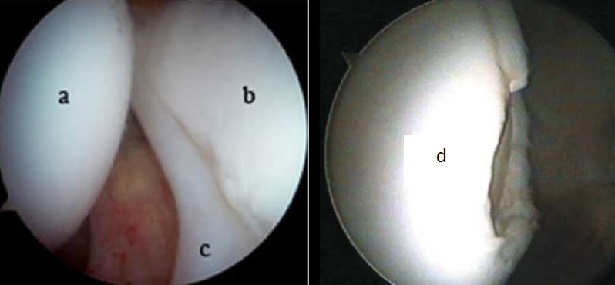

Negli stadi di osteonecrosi ove è già presente un danno condrale dovuto all’infarto osseo è neccessario associare il tempo di riparazione articolare.

Tale procedura artroscopica deve essere eseguita da un chirurgo esperto che riconosca la migliore tecnica di medicina rigenerativa da applicare e che possa inoltre ridurre al minimo il tempo chirurgico.

Tramite due accessi di circa 1 cm si visualizza direttamente la cartilagine articolare, il labrum acetabolare e le lesioni.

Le procedure applicabili hanno l’obiettivo di regolarizzare e riparare i danni per preservare l’articolazione e diminuire il dolore.

In base alla sede della lesione, alle dimensioni ed alle caratteristiche del paziente varie tecniche di medicina rigenerativa vengono infine applicate per determinare uno stimolo biologico riparativo sia all’osso subcondrale che al danno cartilagineo.